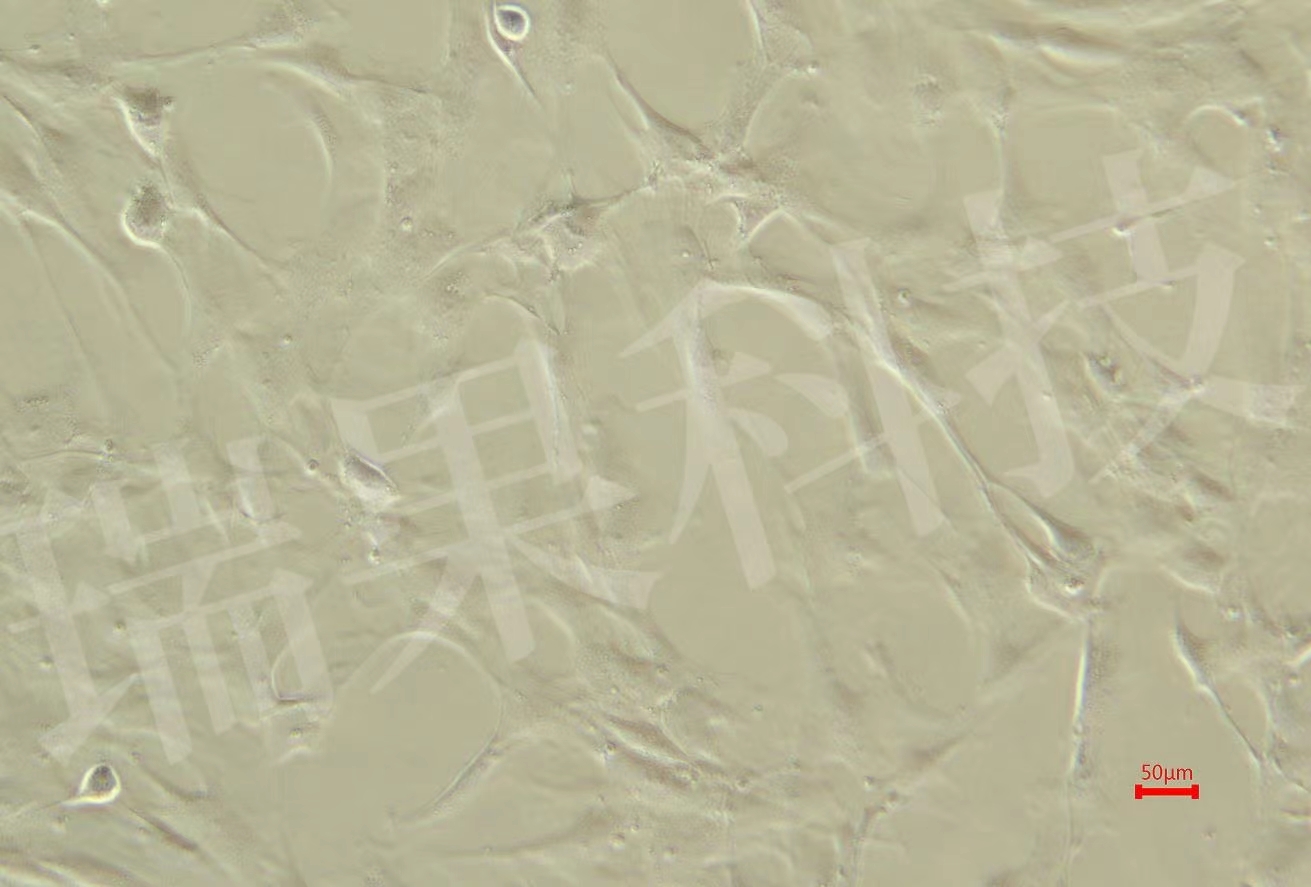

• 肿瘤模型

提供全面、专业的肿瘤动物模型构建与研究服务,覆盖从基础研究...

肿瘤模型